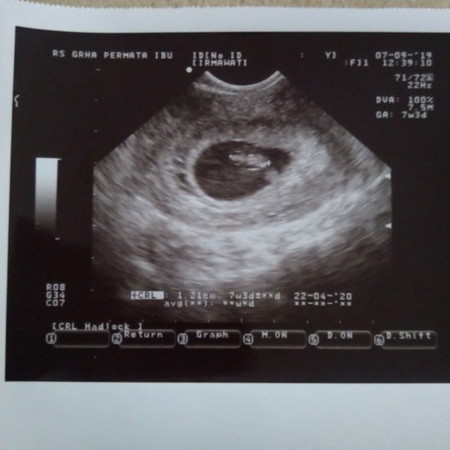

7week3day

bund aku mau tanya, kemarein USG alhamdulillah dd bayinya udh ada, trus aku lupa nanyain udh ada djj nya ap belum, emang biasanya di laya motir itu otomatis ada djj bayinya apa di cari sama dr nya ? apa mungkin emang blum ada djj nya calon dede bayi aku